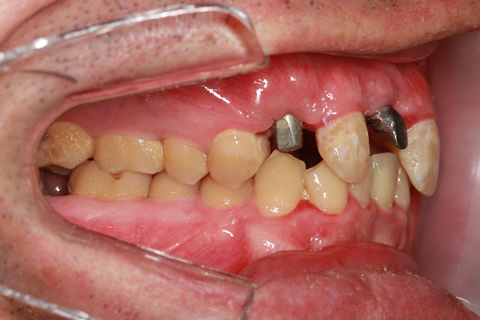

症例2

- 年齢・性別

- 57歳男性

- 治療期間

- 3ヶ月

- 抜歯

- なし

- 治療費

- 165万円

- 備考

- 左上5.6.7 及び左下6.7欠損

- 治療内容

- 左上5.6.7と左下6.7欠損部にインプラント埋入

- 施術の副作用(リスク)

- オペによる知覚障害。インプラントによる歯肉炎。インプラント脱落。